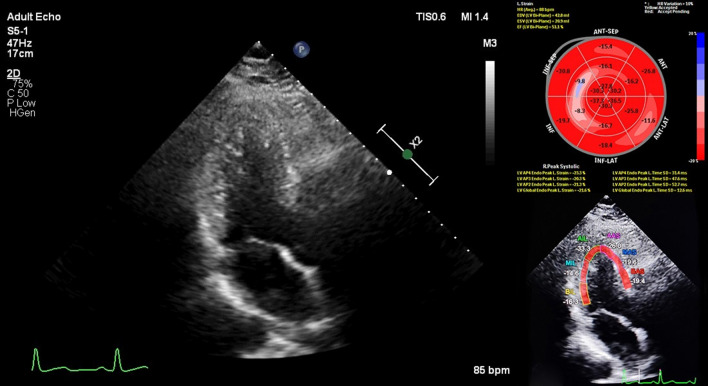

Myocardial GLS was measured using the Philips EPIQ7 machine by using commercially available software (QLAb) for the LV. (Fig. 2) The mean GLS was calculated by averaging the peak GLS values of three apical views (2-, 3- and 4-ch) and automatic endocardial contour tracking was performed in end-systole. The timing of end-systole was determined by aortic valve closure. LVGLS assessment was carried out by a single pyhsician (BBK). The normal limit of GLS, which is expressed as a negative value, was < -18% [7, 10]. In other words, the more negative values demonstrate the better cardiac function.

Fig. 2.

Speckle tracking apical three chamber view showing global longitudinal strain